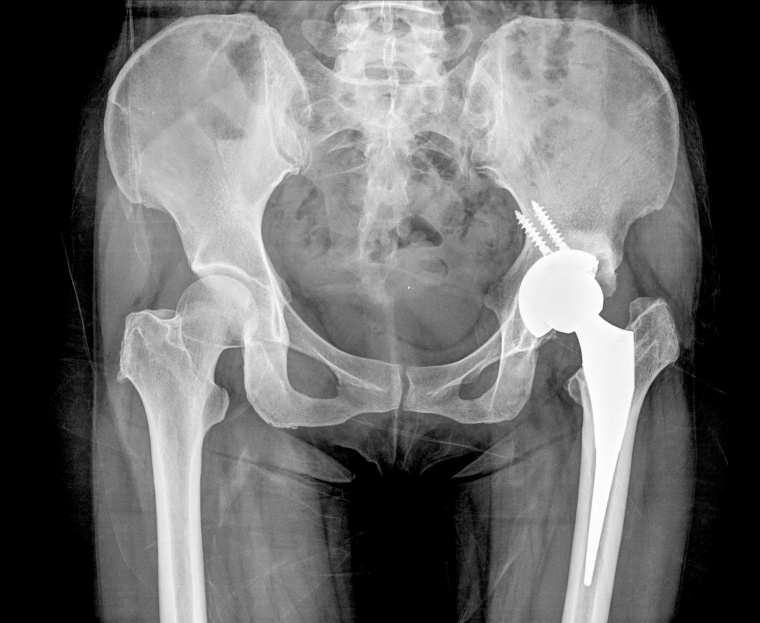

Bei schmerzhaften Bewegungseinschränkungen oder vollständiger Unbeweglichkeit kann eine Arthrose vorliegen. Diese, umgangssprachlich auch als Gelenkverschleiß bezeichnete Erkrankung, schmälert die Lebensqualität der Betroffenen, durch deren eingeschränkte Bewegungsfähigkeit, stark ein. Dadurch können auch weitere Erkrankungen wie Übergewicht, Lungenentzündungen und Diabetes folgen. Wenn die Behandlung mit Schmerzmitteln und Krankengymnastik nicht mehr ausreicht, sollten Betroffene eine Operation mit Einsatz eines Gelenkersatzes in Betracht ziehen.

In Deutschland werden durchschnittlich im Jahr 350.000 Knie- und Hüftgelenke eingesetzt. In der Regel halten Implantate über viele Jahre hinweg. So verbleiben zum Beispiel nach 10 Jahren mehr als 90 % der Implantate im Patienten, ohne dass eine Wechseloperation notwendig geworden ist. Sogar nach 25 Jahren gilt dies noch für den überwiegenden Teil der Implantate. Dennoch können in einigen Fällen Wechseleingriffe nötig sein, zum Beispiel beim Verschleiß von Prothesenteilen. Sowohl das Einsetzen von künstlichen Gelenken, als auch der Austausch werden am Hospital zum Heiligen Geist nach den EndoCert- Standards durchgeführt.